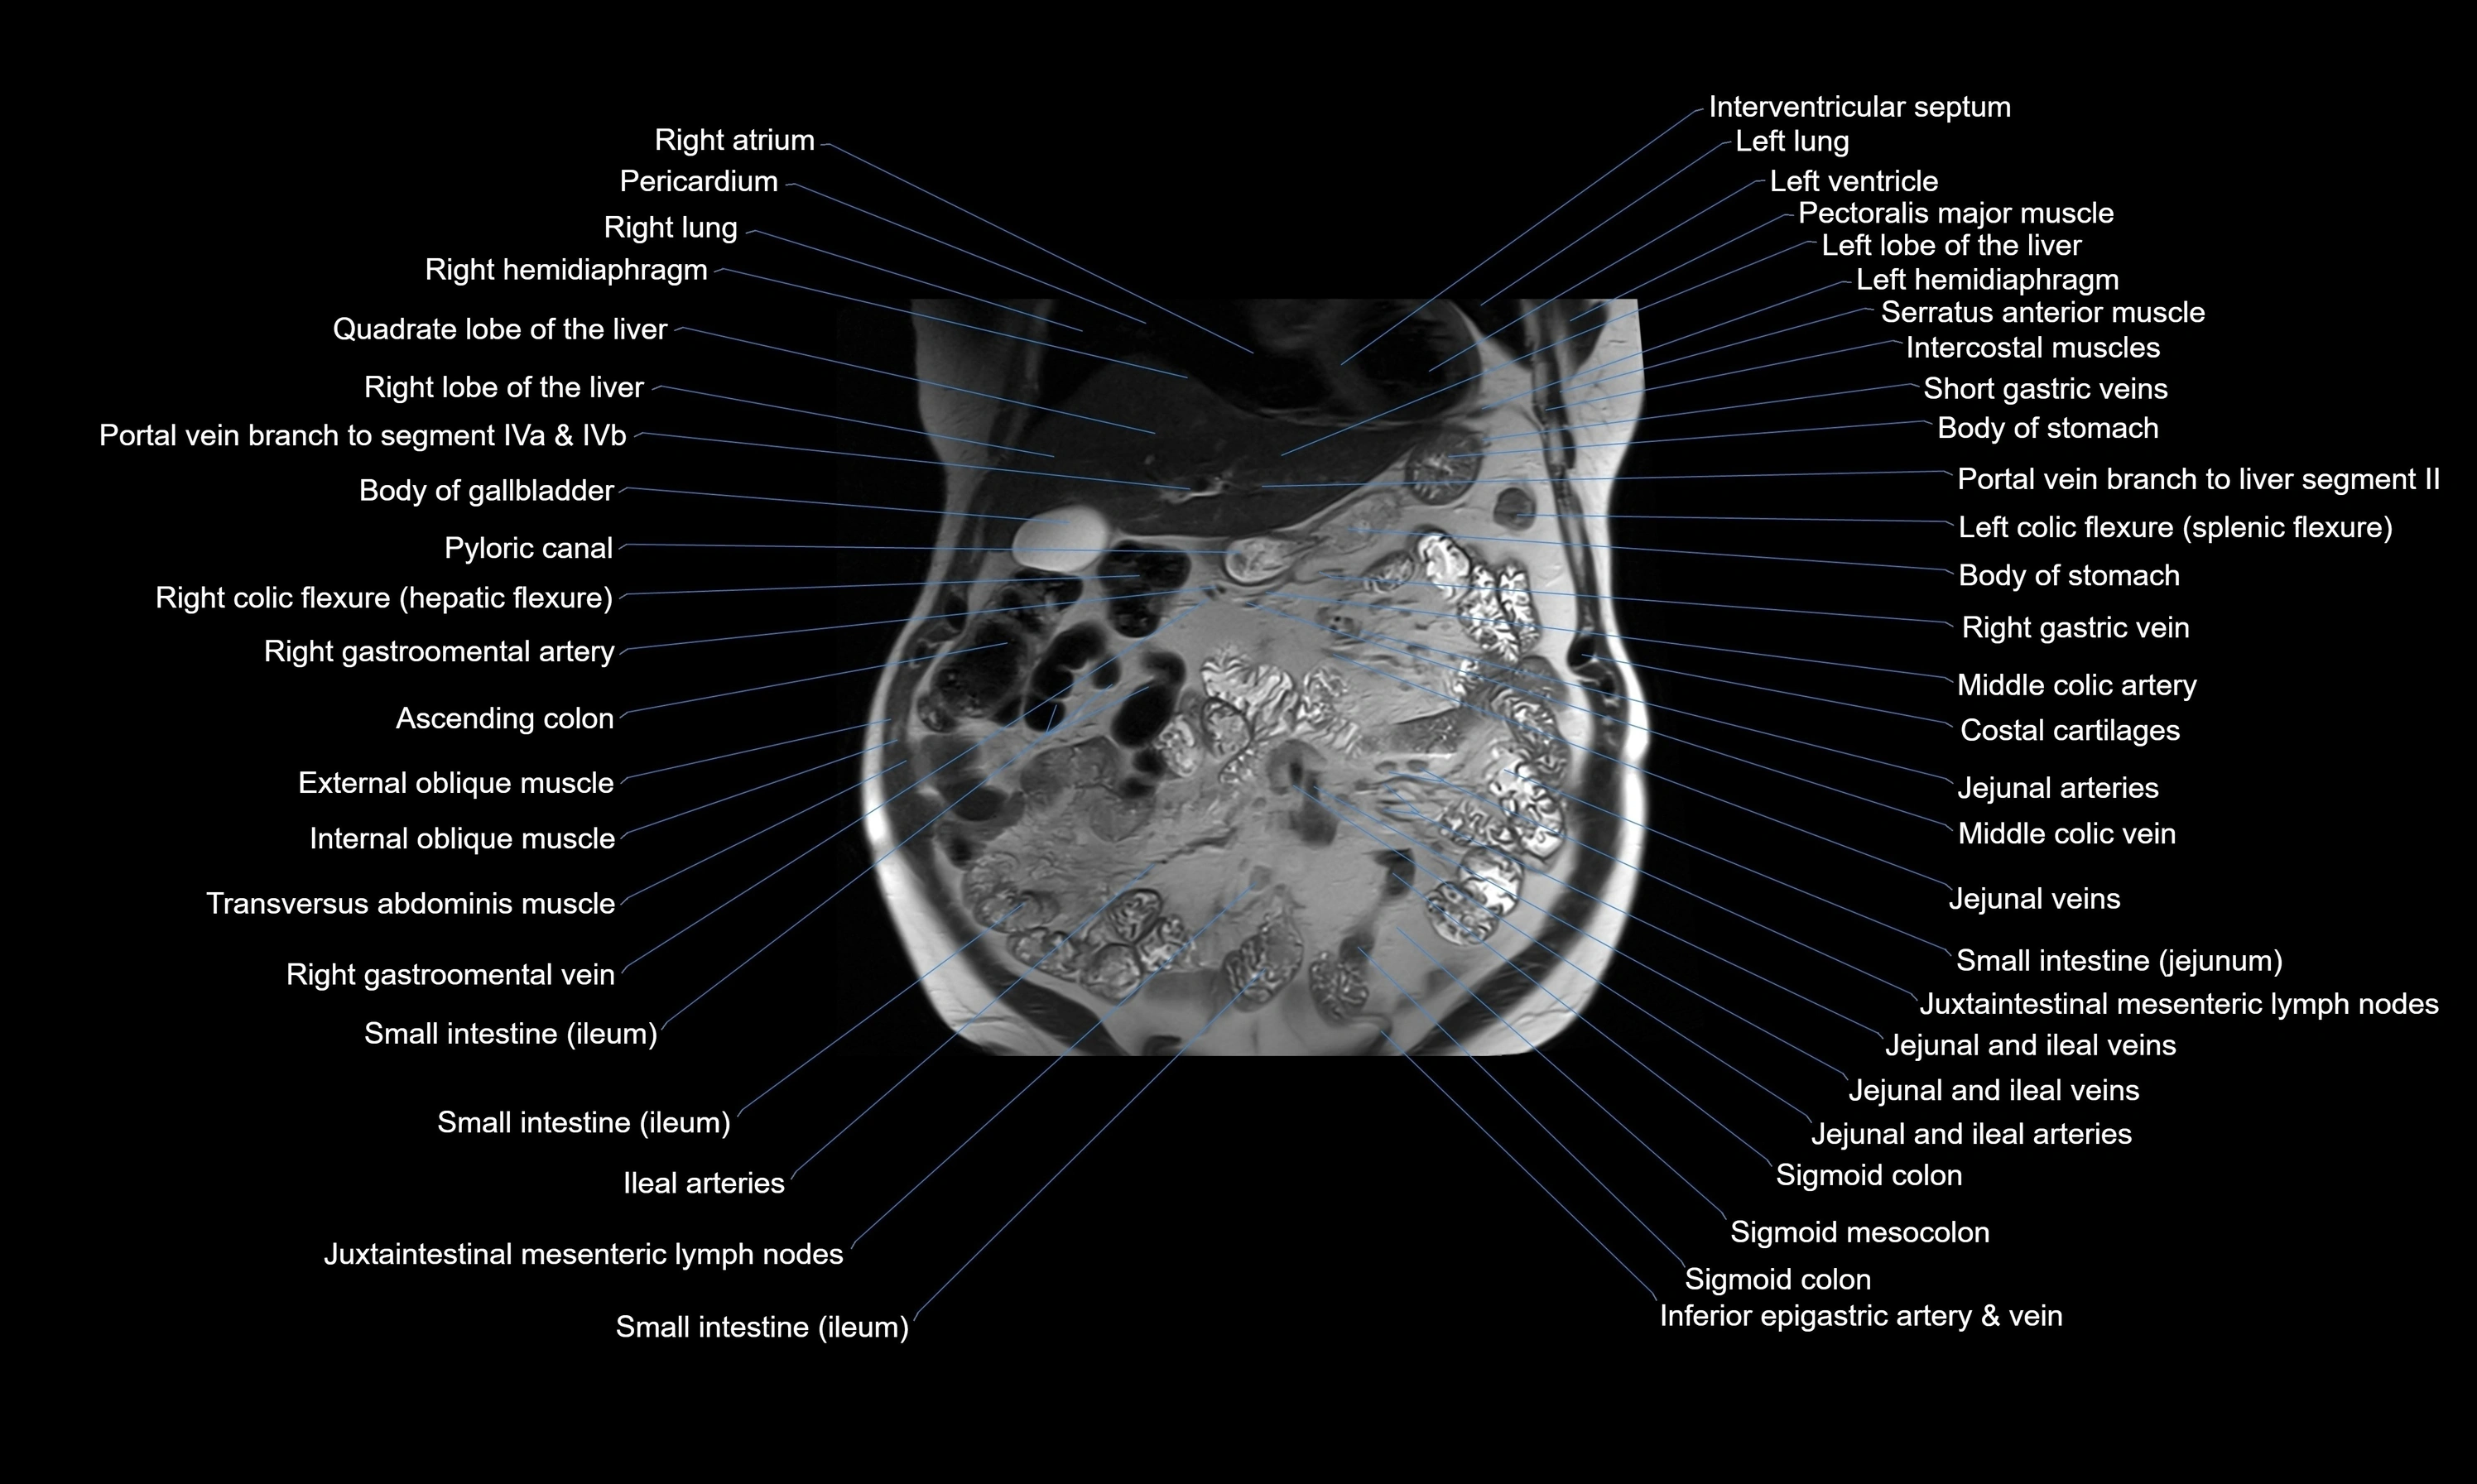

MRI images